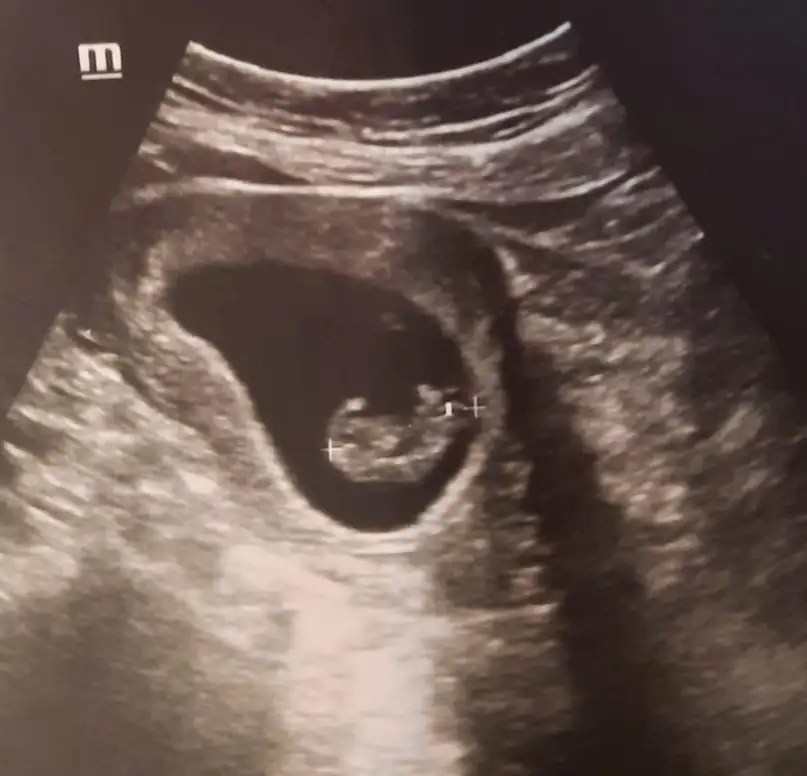

2.foto 11+5